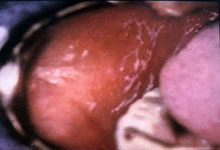

病理特点:

1.上皮改变:

上皮过度正角化或过度不全角化,也可无角化。棘细胞层不规则增厚或萎缩,可同时存在。上皮钉突不规则增生,延伸到固有层,呈“锯齿状”改变,但在口腔粘膜扁平苔藓较少见。基底细胞层水肿、液化变性显著,可见上皮和结缔组织分离,形成上皮下疱。基底膜区界限不清,可见嗜酸带宽约20um,无细胞浸润。

2.固有层改变:

炎细胞浸润主要是淋巴细胞,还有单核细胞、浆细胞和中性粒细胞。炎细胞浸润带与上皮之间界限不清,而与结缔组织之间界限清楚。炎细胞浸润带中细胞密度与分布的宽度较均匀。

3.胶样小体(colloid body or Civatte body):

在上皮的棘层、基底层或粘膜固有层可见圆形或卵圆形的胶样小体,其直径平均为10μm左右,为均质性嗜酸性,PAS染色阳性呈玫瑰红色。这种小体可能是细胞凋亡的一种产物。